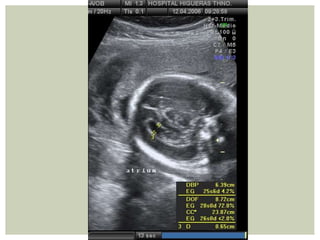

II Trimestre

Septum pel.

tálamo

atrium

EVALUACIÓN ANATOMÍA FETAL

CRÁNEO Y ENCÉFALO

DBP/DOF x 100ÍNDICE CEFÁLICO

NORMAL: 74-83

< 74: DOLICOCEFALIA

> 83: BRAQUICEFALIA